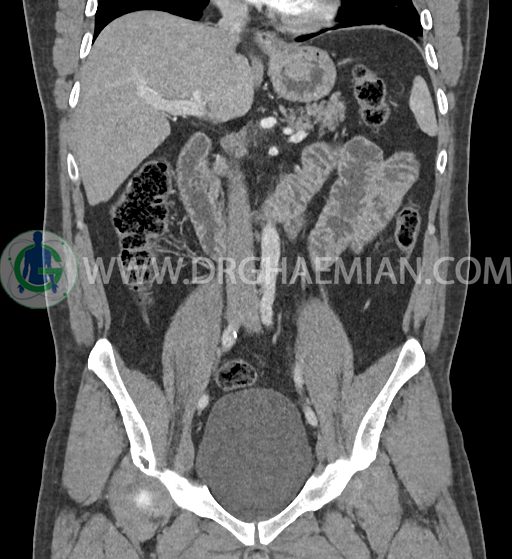

سی تی اسکن شکم و لگن با استفاده از اشعات ایکس تصاویر عرضی از ناحیه شکم و لگن ایجاد میکند. در این کیس فتق هیاتوس و هیدرویورترونفروز دیده می شود.

در سی تی اسکن اسپیرال شکم و لگن با کنتراست خوراکی و وریدی (مولتی دیدکتور 16 با مقاطع ظریف و بازسازی های ساژیتال و کرونال) :

-sliding hiatal hernia به ابعاد 60x44mm با جابجایی JE.junction و فوندوس معده به فضای مدیاستن خلفی دیده می شود.

-هیدرویورترونفروز جزئی دو طرفه دیده می شود که می تواند ثانویه به اتساع مثانه باشد.